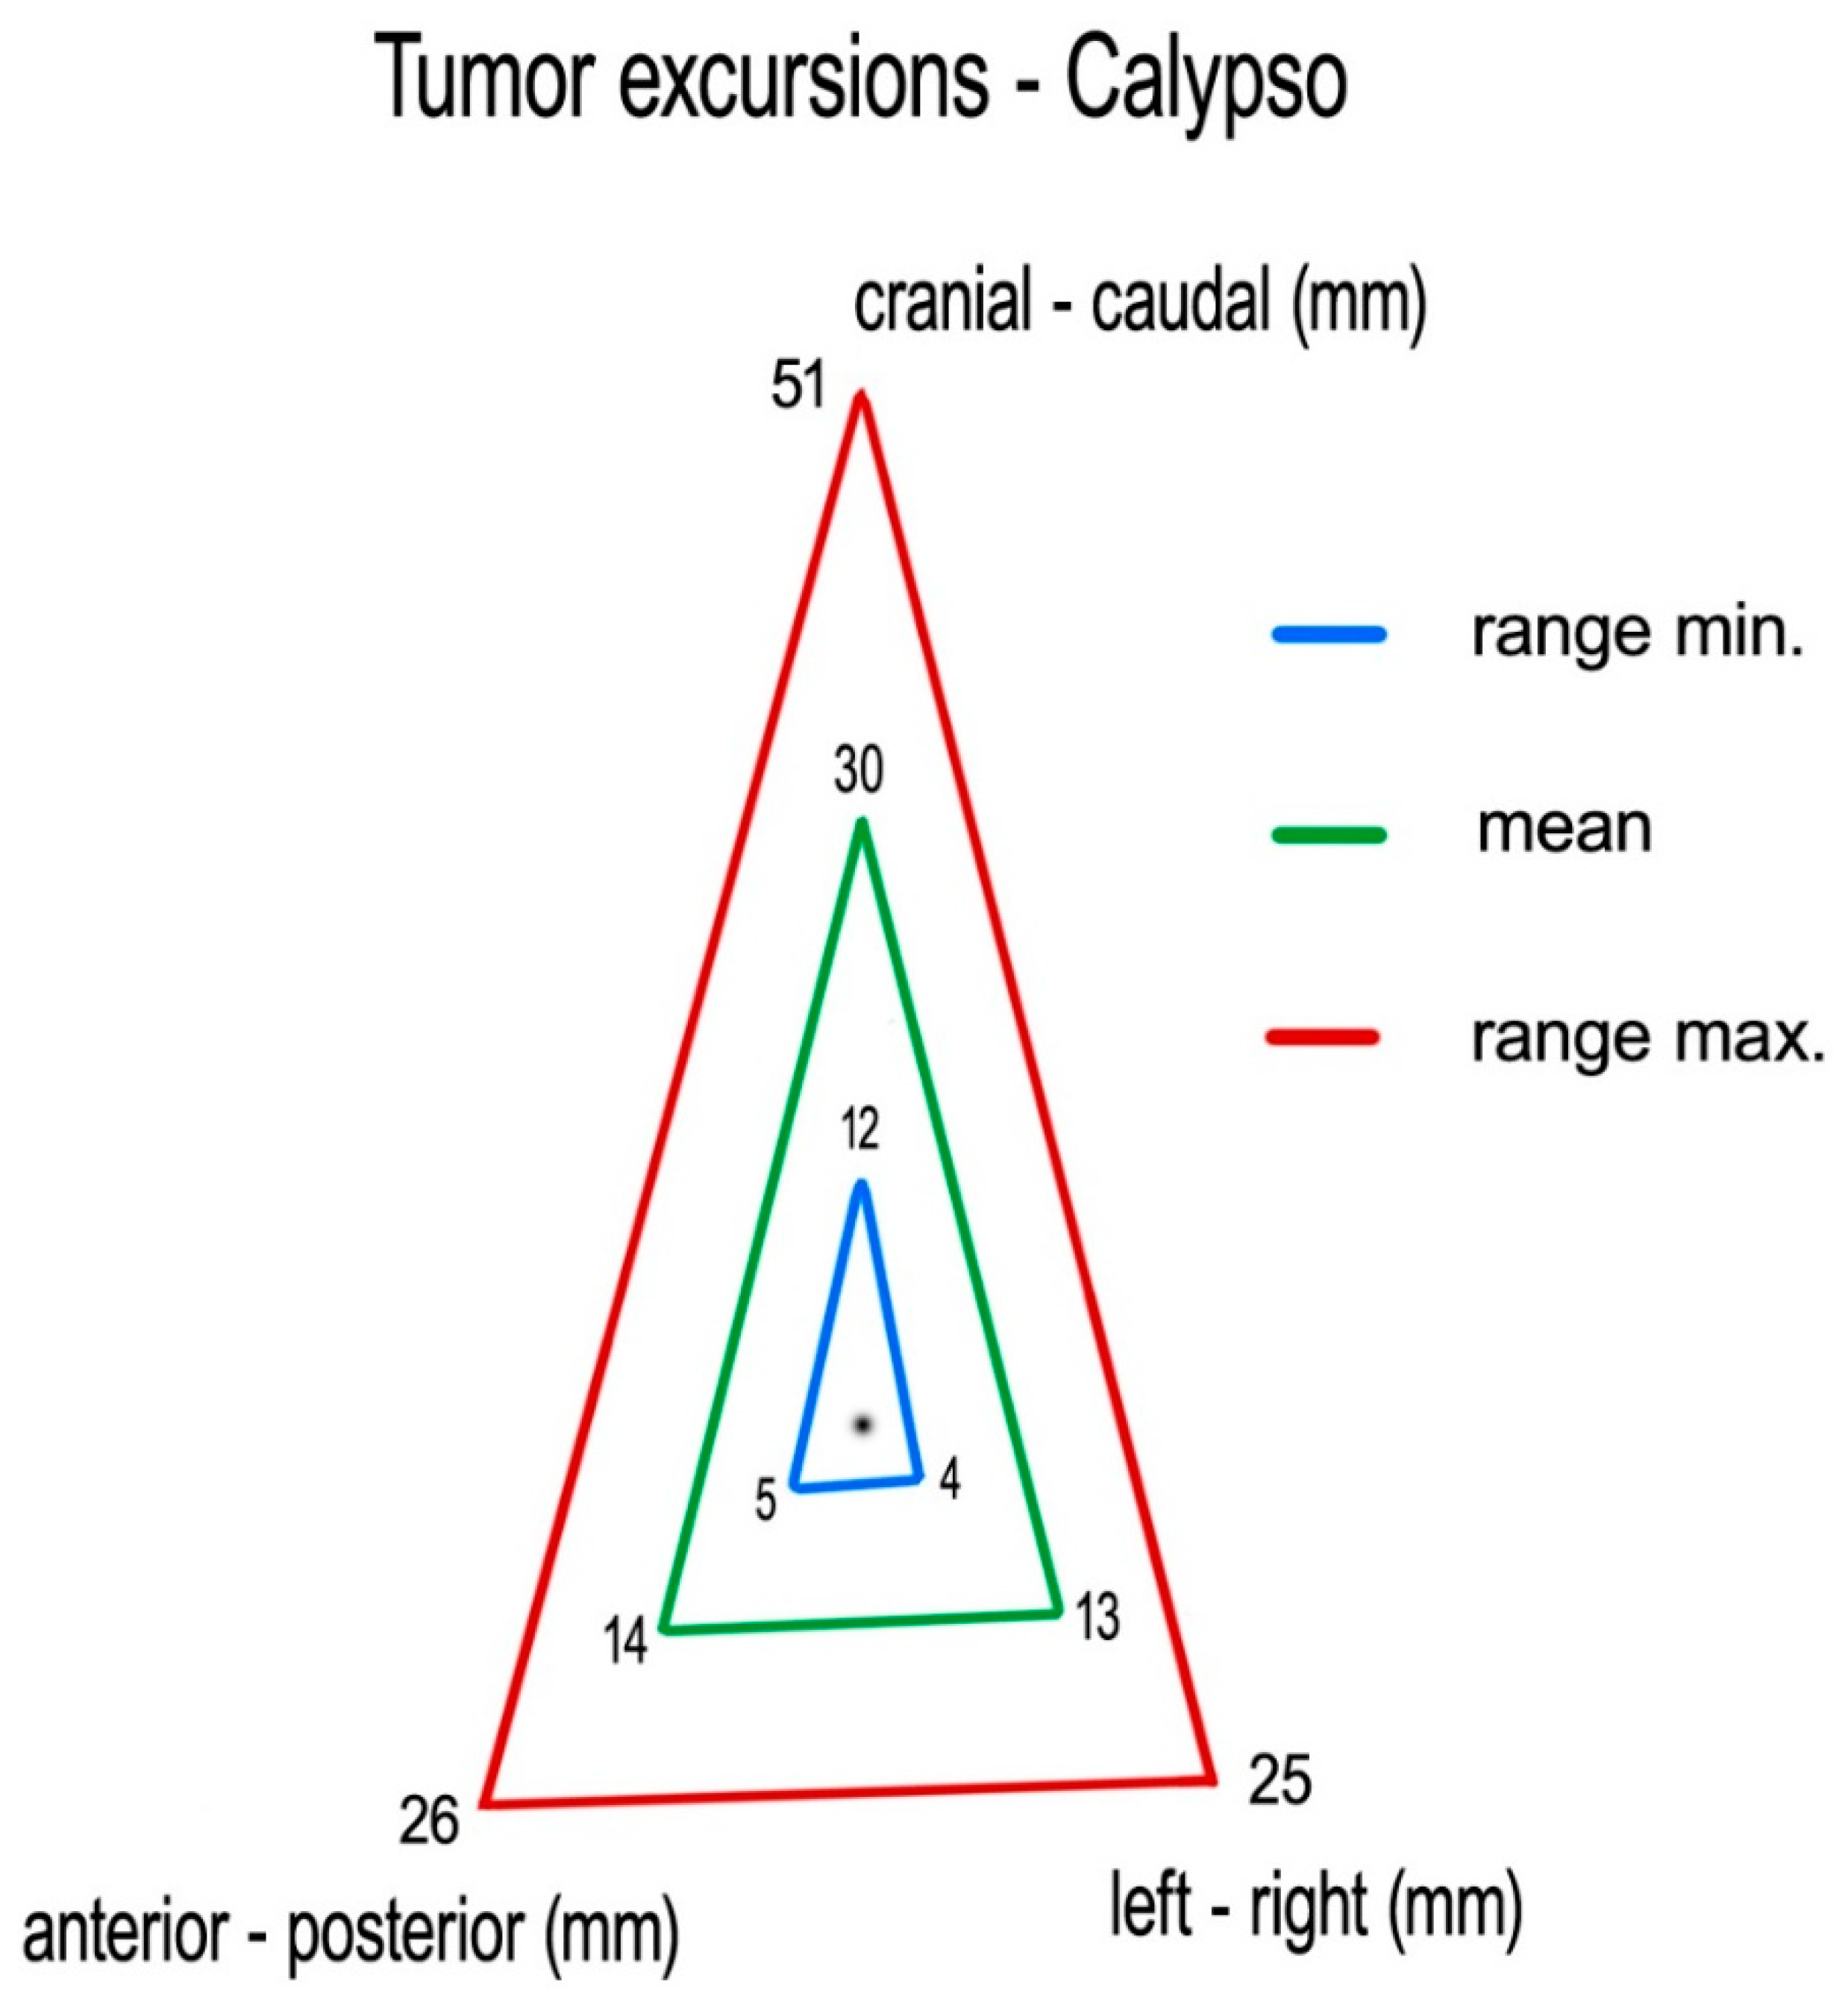

Measuring centroid excursions using Calypso

®, we found the following medians (means) of tumor excursions in the corresponding directions: CC: 29 (30) mm (ranging 12–51 mm), AP: 14 (14) mm (ranging 5–26 mm) and LR: 11 (13) mm (ranging 4–25 mm) (

Figure 5).

Measuring the 4D-CT study sets, we found following medians (means) of tumor excursions in the corresponding directions: CC: 19 (19) mm (ranging 6–35 mm), AP: 9 (9) mm (ranging 0–21 mm), and LR: 9 (10) mm (ranging 3–27 mm) (

Figure 6).

The differences between the Calypso

® and 4D-CT median recordings of maximal tumor excursion were in the CC, AP and LR directions 10 mm, 5 mm and 2 mm, respectively. The median c-ITV was 110% larger than the median ITV. The results of the descriptive statistics are presented in

Our goal was to determine the total extent of the internal motions of pancreatic cancer. The results of our study indicated, in general, significantly larger pancreatic tumor maximal excursions measured with Calypso® extracranial tracking than those previously observed, with medians (range) in following directions: CC: 29 mm (1.2–5.1 mm), AP: 14 mm (5–26 mm) and LR: 11 mm (4–25 mm). The results of the pancreatic tumor motions recorded with 4D-CT were approximate to those presented in previous published studies (medians): CC: 19 mm, AP: 9 mm, and LR: 9 mm. The medians of tumor excursions recorded using Calypso® extracranial tracking were 53% larger in the CC direction, 56% larger in the AP direction, and 22% larger in the LR direction, compared to excursions recorded using 4D-CT, and the median Calypso®-based ITV was 110% larger than the median 4D-CT-based ITV.